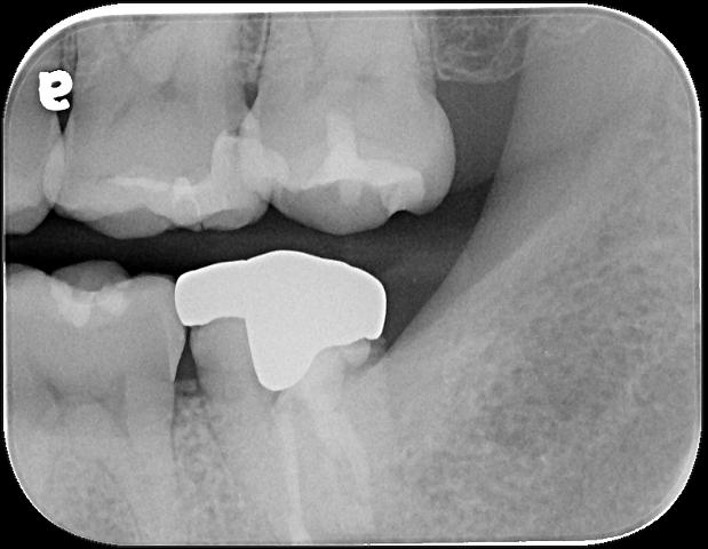

治療前,二次蛀牙

蛀牙未到牙髓